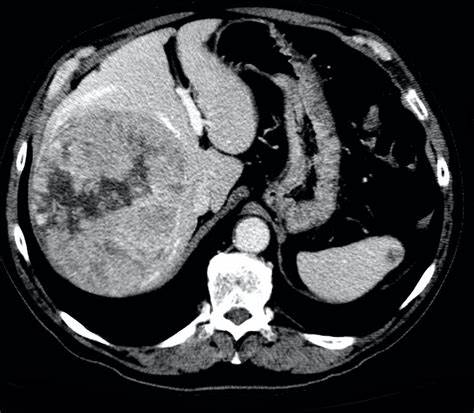

文章图片